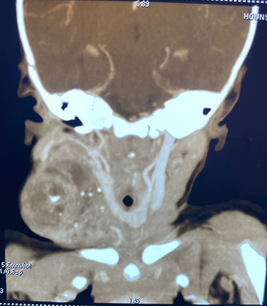

3-year-old female child with no pathological history seen in consultation for right side-cervical mass. Congenital swelling gradually increasing in volume since birth without respiratory effects. On examination, the child presents a good general condition, a right side-cervical mass of firm, bumpy consistency measuring 5 x 6 centimeters filling the supraclavicular hollow (Figure 1). A cervical CT scan is performed which reveals a tissue mass without signs of compression of the ipsilateral jugulo-carotid axis (Figure 2). Orotracheal intubation and one-piece surgical excision of the tumor are carried out under general anesthesia (Figures 3 and 4). Pathological examination of the surgical specimen concluded that it was a mature teratoma with no signs of malignancy (Figure 5). The postoperative course was simple with the alpha fetoprotein level normalizing at 6 months.

Figure 2 CT section showing the mass and its relationships.

The development of multi-scanners with sub-millimeter sections and multi-planar reconstructions allows a better study of fleshy and fatty tissue components and in particular calcifications which are poorly explored in MRI.9 The scanner also allows a detailed study of the relationships, particularly with the jugulo-carotid vascular axis, as well as an objective assessment of the impact on the aerodigestive system.10 This examination carried out for our patient provided all the information necessary for safe surgery.